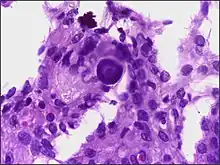

- A woven architectural pattern

- Psammoma bodies (spheroid calcifications)

- Syncytial cells (having indistinct cell membranes) with eosinophilic (pink) cytoplasms

- Round uniform nuclei

- Whorls (concentric cell arrangements)[15]

Histologically, meningioma cells are relatively uniform, with a tendency to encircle one another, forming whorls and psammoma bodies (laminated calcific concretions).[18] As such, they also have a tendency to calcify and are highly vascularized.